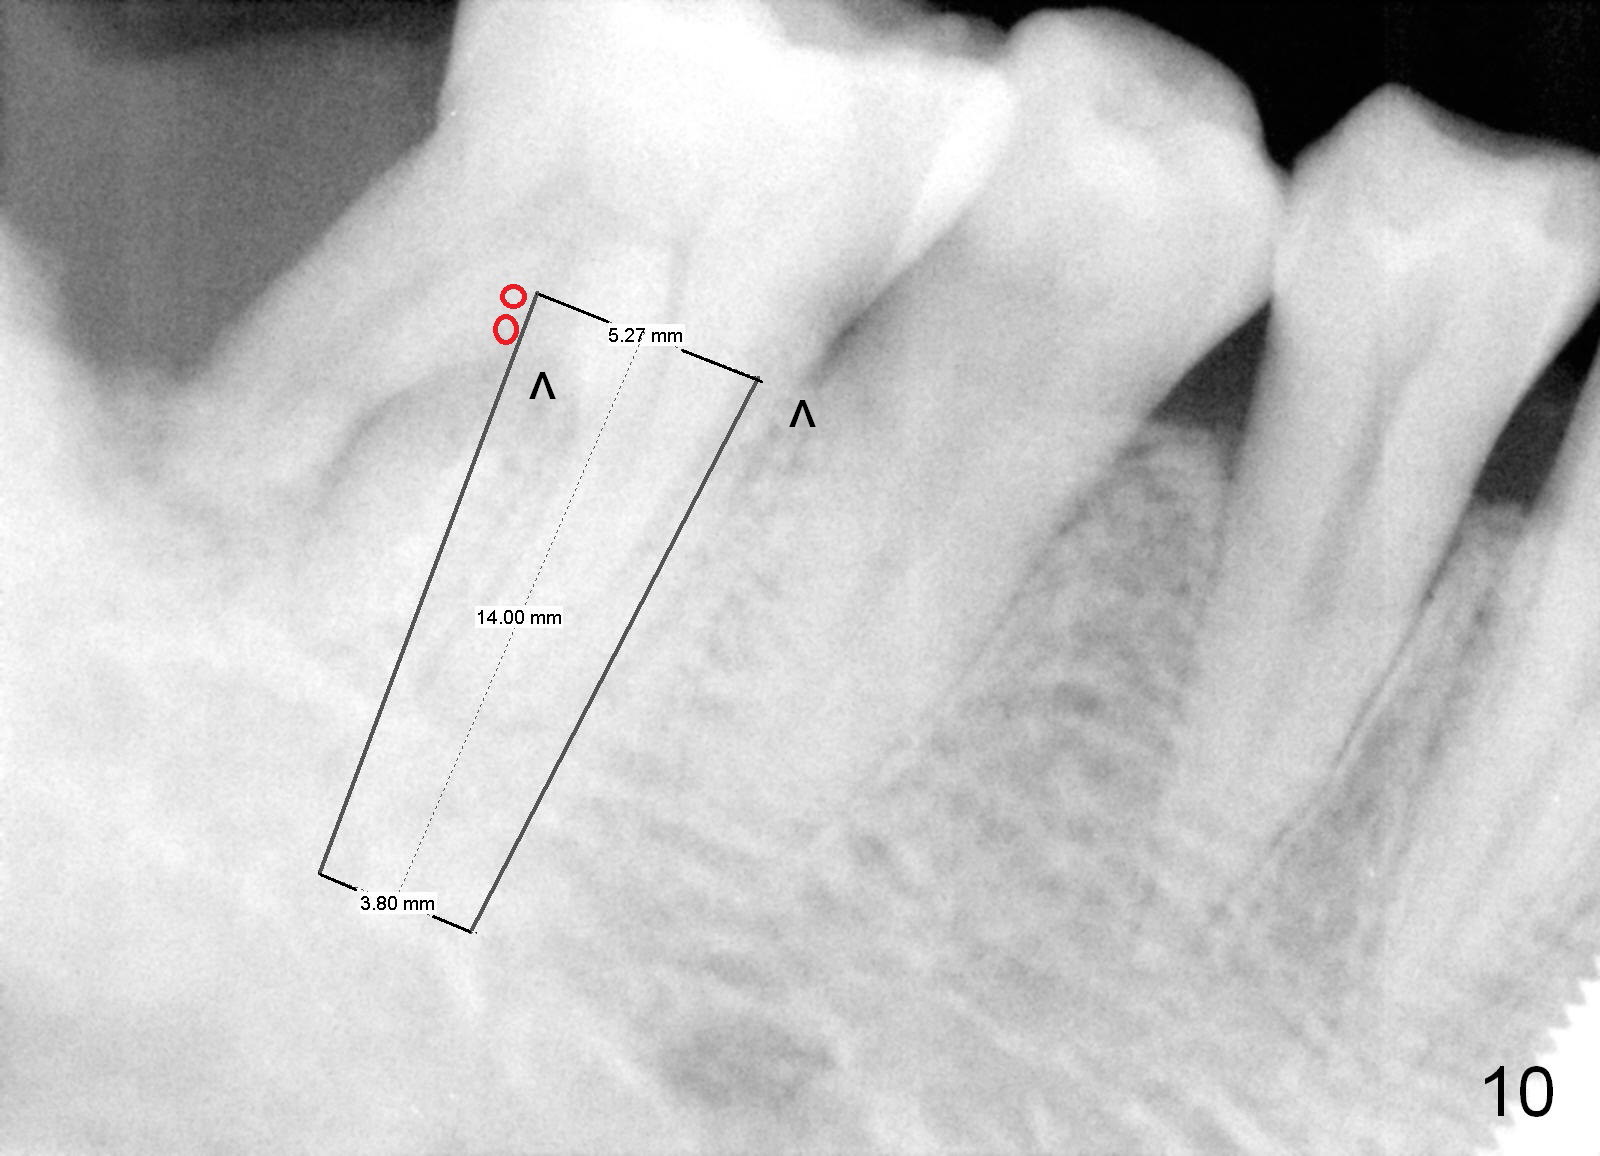

Fig.6 is an illustration after extraction (S: septum; M: mesial socket). Osteotomy is initiated with a pilot drill in the distal aspect of the mesial socket or the mesial aspect of the septum (Fig.7). The osteotomy is enlarged with osteotomes; at the same time the septum is being pushed distally (Fig.8 blue arrow) with leaning the osteotomes distally (white arrow). When an implant is placed, the apex is mainly seated in the mesial socket, while the coronal end is more or less inclined distally for restoration. The apical half of the distal sockets is packed with collagen plug or dressing, whereas the remaining sockets and coronal exposed threads are filled with bone graft (Fig.9,10 red circles). An incision is made if needed for better visibility. The most coronal socket is going to be obliterated by a cemented or healing abutment. Does the treatment planning help surgery?